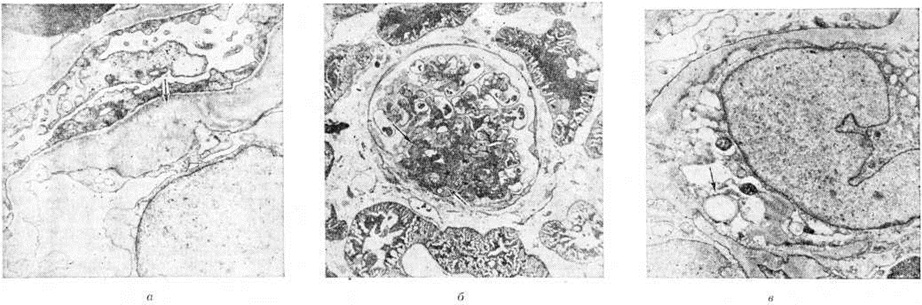

Морфологически основой при вторичном Нефротический синдром может быть специфическая нефропатия (волчаночная, ревматоидная и другие), амилоидоз почек, гломерулонефрит или сочетанная патология (как при узелковом периартериите). Поэтому гистологический картина при световой, иммунофлюоресцентной и электронной микроскопии отражает признаки не только самого Нефротический синдром, но и изменения, свойственные названным заболеваниям. Большинство заболеваний, обусловливающих Нефротический синдром, возникает на иммунной основе, то есть вследствие осаждения в органах (в том числе в почках) иммунных комплексов или вследствие взаимодействия антител с антигенами базальной мембраны капилляров клубочков с сопутствующими нарушениями клеточного иммунитета. Последние проявляются в реакциях органоспецифической гиперчувствительности замедленного типа и в ослаблении контролирующего пула Т-лимфоцитов. Иммунные механизмы активируют гуморальные и клеточные звенья воспалительной реакции и сосудистой проницаемости с развитием клеточной эмиграции, фагоцитоза, дегрануляции лейкоцитов и освобождением при этом лизосомальных ферментов, способных повреждать структуры тканей (смотри полный свод знаний Воспаление). Антигены, входящие в состав иммунных комплексов, могут быть экзо и эндогенными. К экзогенным относят антигены бактериальные, вирусные, паразитарные, медикаментозные, пищевые, пыльцу растений, соединения тяжёлых металлов и другие Эндогенными антигенами при ряде заболеваний могут стать тиреоглобулин, ДНК, денатурированные нуклеопротеиды, криоглобулины, белки опухолевого происхождения. Антитела к этим антигенам в большинстве случаев принадлежат к классу IgM или одновременно к нескольким классам Ig. Величина иммунных комплексов зависит от характера антигена и связанных с ним антител. Малые комплексы обыкновенно содержат избыток антигенов и растворимы. Большие комплексы, мол. вес которых больше 50 000, содержат избыток антител, легко депонируются в стенках микрососудов органов, в том числе почек, вызывая развитие вторичных воспалительных реакций (нефропатий). Степень поражений органа зависит от концентрации комплексов, их состава и продолжительности антигенной стимуляции. Однако не все заболевания, вызывающие Нефротический синдром, имеют доказанный иммунокомплексный генез. Так, не ясен патогенез липоидного нефроза, врождённого Нефротический синдром финского типа, Нефротический синдром при таких генетически обусловленных болезнях, как мукополисахаридозы или парциальная липодистрофия. Изучаются иммуногенетические аспекты патогенеза Нефротический синдром различного происхождения. Типирование по системе HLA больных с Нефротический синдром показало существенное преобладание определённых антигенов системы гистосовместимости при ряде нозологических форм нефротического синдрома: при нефротическом синдроме на почве геморрагического васкулита преобладали HLA—BW35, среди больных с атопическим Нефротический синдром у большей половины выявляли HLA—В12, при системной красной волчанке — HLA—38. Однако, по данным Томсона (P. D. Thomson) с соавторами (1976) и Шерака (Одонтома Scherak) с соавторами (1978), корреляции между клиническими, иммунологическими показателями и теми или иными антигенами системы HLA выявлено не было. Если иммунологический концепция патогенеза применима для большинства нозологических форм, течение которых осложняет Нефротический синдром, то механизмы большой нефротической протеинурии нельзя признать окончательно выясненными. Определёнными вехами в учении о патогенезе Нефротический синдром являются: концепция обменно-дискразическая; концепция эндокринной недостаточности; иммунологическая (в большей мере применимая к обусловливающей Нефротический синдром нефропатии); метаболическая, или физико-химическая, являющаяся наиболее признанной. Отправным пунктом метаболической концепции патогенеза является общепризнанный факт, что нефротическая протеинурия обусловлена главным образом усиленной проницаемостью клубочкового фильтра. Усиление клубочковой проницаемости при Нефротический синдром, как установлено, прежде всего связано с уменьшением постоянного электрического заряда стенки капиллярной петли. Последнее обусловлено исчезновением из неё сиалопротеина, в норме тонким слоем покрывающего эндотелий и его отростки, лежащие на базальной мембране, и входящего также в состав самой мембраны. Исследование химический состава базальных мембран при различных формах нефротического синдрома позволило установить увеличение содержания коллагена в базальной мембране и активности ферментов, принимающих участие в его синтезе, а также уменьшение содержания в ней 3-гидроксипролина, 4-гидроксипролина, глицина. Предполагается, что на местах максимальной потери анионов скапливаются полиморфно-ядерные лейкоциты, лизосомальные ферменты которых разрушают материал базальной мембраны, вследствие чего в мочу поступают фрагменты клубочковой базальной мембраны. Изменённые, распластанные по базальной мембране подоциты (размеры их могут быть в 7—15 раз больше по сравнению с нормой) не полностью закрывают места разрушения, через которые и происходит утечка высокомолекулярного белка. Синтез вещества базальной мембраны подоцитами и (или) мезангиальными клетками снижен и извращён. При большой фильтрации белков через мембраны капилляров клубочков проксимальные канальцы не в состоянии реабсорбировать и деградировать белок, что ведёт к развитию тяжёлой гиалиново-капельной и вакуольной дистрофии эпителия. Патологическая анатомияПри нефротическом синдроме первичными являются изменения гломерулярного фильтра, с ними связана нарастающая протеинурия. Изменения канальцев, стромы, сосудов вторичны и развиваются в связи с реабсорбционной тубулоинтерстициальной недостаточностью и со все возрастающей в этих условиях гипоксией почечной ткани. Изменения почек при Нефротический синдром, рассматриваемые как протеинурические повреждения, хорошо прослеживаются в динамике на ультраструктурном и клеточном уровнях. Протеинурия, обусловленная избыточной фильтрацией белков плазмы, превосходящей реабсорбционные возможности канальцевого эпителия, вызывает структурную перестройку гломерулярного фильтра и канальцевого аппарата. При протеинурии в цитоплазме подоцитов появляется множество пиноцитозных пузырьков, выявляется хорошо развитая цитоплазматическая сеть, обилие рибосом и полисом, усиливается фибриллярный рисунок цитоплазмы, причём фибриллы ориентированы по оси возможного сокращения клеток-насосов (рисунок 1). Эти ультраструктурные изменения свидетельствуют о повышенной функциональный активности подоцитов. Декомпенсация функции подоцитов ведёт к повреждению эндотелия, он вакуолизируется, набухает, происходит его десквамация, что сопровождается компенсаторной пролиферацией клеток эндотелия. Повреждение гломерулярного фильтра сопровождается адаптивной гиперплазией мезангиальных клеток, продуцирующих мембраноподобное вещество мезангиального матрикса и вещество базальной мембраны. Отложение этого вещества в мезангии и очаговое утолщение базальной мембраны вблизи активных мезангиальных клеток дополняют структурную адаптивную перестройку гломерулярного фильтра при Нефротический синдром

Морфологически эквивалентом протеинурии и истощения резорбтивной функции эпителия канальцев является гиалиново-капельная, вакуольная, баллонная и жировая дистрофия эпителия (цветной рисунок 1, 2, 3), при которых активность .ферментов в эпителии нефронов резко снижена (смотри полный свод знаний Дистрофия клеток и тканей). Электронно-микроскопически обнаруживаются набухание, вакуолизация и распад митохондрий, разрыв цистерн цитоплазматической сети, разрушение мембран. В результате дистрофических процессов развивается некробиоз и десквамация эпителия, которые являются основой формирования цилиндров, обтурирующих просветы канальцев, что приводит к кистозному их расширению и атрофии. Отражением функциональный недостаточности лимфатических, системы почек — второй системы реабсорбции при Нефротический синдром служит отёк интерстиция, который быстро сменяется склерозом, причём среди разрастаний соединительной ткани часто встречаются большие светлые клетки с пенистой цитоплазмой (рисунок 2), которые считают макрофагами, фагоцитировавшими липиды. В сосудах почек находят плазматическое пропитывание и гиалиноз, склероз стенок. Первичный нефротический синдром. Морфология первичного Нефротический синдром складывается из изменений, характерных для следующих его форм: липоидный нефроз, фокальный сегментарный гломерулярный гиалиноз, мембранозный гломерулонефрит (мембранозная нефропатия), врождённый Нефротический синдром (сведения о нем см. ниже). Липоидный нефроз (синонимы: идиопатический Нефротический синдром детей, нефропатия с минимальными изменениями) описан впервые Мунком (F. Munk, 1913), который обнаружил в моче больных и в эпителии канальцев липиды. Он полагал, что изменения в почках связаны с общими нарушениями обмена. Долгое время термины «липоидный нефроз», «мембранозный гломерулонефрит», «второй тип нефрита Эллиса», «нефротический синдром» употреблялись как синонимы. Благодаря работам Джонса (D. В. Jones, 1957) было выделено несколько форм Нефротический синдром: минимальные гломерулярные изменения, мембранозный гломерулонефрит и лобулярный гломерулонефрит. Название «липоидный нефроз» было оставлено только для обозначения своеобразной патологии детей, проявляющейся Нефротический синдром с минимальными изменениями в клубочках почек, выявляемых при светооптическом исследовании. Термины «липоидный нефроз» и «минимальные изменения» стали использоваться как синонимы. Сущность минимальных изменений установлена с помощью электронной микроскопии материала биопсии почек. При липоидном нефрозе изменяются только подоциты, у которых происходит слияние малых отростков, базальная мембрана при этом остаётся неизменённой (рисунок 3, а). После нескольких лет болезни к минимальным изменениям присоединяется очаговое утолщение базальных мембран капилляров (рисунок 3, б), увеличение мезангиального матрикса или количества мезангиальных клеток. Если заболевание ведёт к почечной недостаточности, в клубочках обнаруживают фокальный сегментарный склероз капилляров. В эпителии проксимальных канальцев на ранних стадиях болезни выявляют двоякопреломляющие липиды и гранулы резорбированного белка. Со временем липиды исчезают из эпителия, появляются признаки атрофии канальцев, которая никогда не бывает значительной. Интерстиций ночек отёчен, к отеку присоединяется разрастание соединительной ткани, в которой находят пенистые клетки. При длительном течении болезни встречается утолщение внутренней оболочки сосудов. Вид почек при липоидном нефрозе, протекающем без почечной недостаточности, характерен: они увеличены, очень бледные, поверхность их гладкая, на разрезе ткань набухшая, отёчная, жёлто-белая или бледно-серая — большая белая почка (смотри полный свод знаний Гломерулонефрит). В случаях смерти от почечной недостаточности почки немного уменьшены, плотные, поверхность их гладкая; ткань почек серого цвета, на разрезе выявляется жёлтая пятнистость. Фокальный сегментарный гломерулярный гиалиноз (очаговый склерозирующий гломерулонефрит) характеризуется преимущественным поражением юкстамедуллярных клубочков. Характерные для него изменения в виде сегментарного склероза впервые были описаны Ричем (A. R. Rich, 1957) у детей с липоидным нефрозом. Позднее Хабиб (R. Habib) с соавторами (1971) предложили для названия этих изменений термин «сегментарный гиалиноз». В процесс вовлекаются отдельные юкстамедуллярные клубочки (фокальные изменения), в которых склерозируются отдельные сегменты сосудистого пучка (сегментарные изменения); остальные клубочки интактны. В начале заболевания на светооптическом уровне изменения оцениваются как минимальные; электронно-микроскопически в материале биопсии почки находят характерные изменения базальной мембраны капилляров: неровные контуры эндотелиальной поверхности базальной мембраны (рисунок 4, а). При выраженной морфологический картине в отдельных капиллярах клубочков появляется гиалиновый материал в виде шаровидных отложений, обычно тесно связанных с капсулой клубочка (рисунок 4, б). В клубочках обнаруживаются пенистые клетки — мезангиальные клетки, содержащие липиды (рисунок 4, в) такие же клетки появляются и в интерстиции. При иммуногистохимическом исследовании в капиллярах клубочков находят IgM, поэтому не исключают участия первичного иммунного механизма в развитии гломерулярных изменений. По мере усиления интенсивности болезни в процесс вовлекаются клубочки поверхностных отделов коркового вещества. Сначала развивается склероз отдельных сосудистых петель, затем он охватывает все сосудистые петли клубочка (глобальный склероз). В канальцах находят жировую и белковую дистрофию эпителия, гиалиновые цилиндры в просветах, встречаются мелкие очаги кальцификации. Патогномонично образование очагов коллапса и атрофии канальцев, сопровождающееся склерозом стромы. Распространённость изменений канальцев пропорциональна выраженности изменений в клубочках. Макроскопический вид почек тот же, что и при липоидном нефрозе. Мембранозный гломерулонефрит характеризуется различными морфологический изменениями (смотри полный свод знаний Гломерулонефрит). Вторичный нефротический синдром. Морфологической основой вторичного Нефротический синдром является гломерулонефрит, который может быть первичный или вторичный (при малярии, лейшманиозе, бактериальном эндокардите, ревматизме, системной красной волчанке, узелковом периартериите, геморрагическом васкулите, нефропатии беременных, гепатите, циррозе печени, тромбозе почечных вен, опухолях и так далее). По своему генезу в большинстве случаев это иммунокомплексный гломерулонефрит, обычно с подострым и хроническим, иногда острым течением. Гистологически при таком гломерулонефрите выявляются различные типы, однако преобладают экстракапиллярный продуктивный, мембранозный, мезангиокапиллярный и фибропластический; определённую специфику имеет волчаночный нефрит. Гломерулонефрит антительного генеза при Нефротический синдром встречается редко, прежде всего при синдроме Гудпасчера. В таких случаях при гистологический исследовании находят пролиферативный экстра или интракапиллярный типы гломерулонефрита. При Нефротический синдром, осложняющем гломерулонефрит любого генеза, резко выражены дистрофические изменения канальцев, слущивание эпителия, образование цилиндров. В тех случаях, когда резко выражена гидропическая дистрофия канальцевого эпителия, принято говорить о гидропическом нефрозе. Его описывали при туберкулёзе, эндокринопатиях, авитаминозах, голодании, но особенно часто при хронический поражениях кишечника, сопровождающихся диареей (нефроз кишечного истощения). При хроническом пиелонефрите развитие Нефротический синдром связано не столько с тубулоинтерстициальными изменениями, сколько с инвазивным гломерулитом, ведущим к тяжёлым изменениям базальной мембраны и подоцитов гломерулярного фильтра. Амилоидоз (смотри полный свод знаний), как и гломерулонефрит, одинаково часто является основным морфологический проявлением вторичного Нефротический синдром, причём именно нефропатический тип амилоидоза (амилоидоз почек, или амилоидный нефроз), независимо от того, является ли он первичным, генетическим, или вторичным. Развитие Нефротический синдром при амилоидозе связано с появлением амилоидного вещества в гломерулярном фильтре, при этохамилоидобластами, продуцирующими белок фибрилл амилоида, становятся мезангиальные клетки. Появлению амилоида в клубочках предшествует амилоидоз и склероз мозгового вещества и пограничного слоя почек, что ведёт к выключению и атрофии глубоко расположенных нефронов, редукции путей юкстамедуллярного кровотока и пирамидного лимфотока. Развивается гиалиново-капельная или вакуольная дистрофия эпителия канальцев: почки увеличиваются в размерах, становятся плотными; поверхность их бледно-серая или жёлто-серая. На разрезе корковое вещество широкое, матовое, мозговое вещество серо-розовое, сального вида (большая сальная почка — рисунок 5). При нарастании протеинурии и переходе протеинурической стадии амилоидоза почек в нефротическую стадию количество амилоида в почках увеличивается. Он обнаруживается во многих капиллярных петлях большинства клубочков, в артериолах и артериях, по ходу собственных мембран канальцев, но выраженные склеротические изменения коркового вещества отсутствуют. В пирамидах, наоборот, склероз и амилоидоз имеют диффузный характер. В эпителии канальцев наряду с гиалиново-капельной и вакуольной отмечается жировая дистрофия. В эпителии канальцев и строме много двоякопреломляющих липидов (холестерина). Канальцы расширены, забиты цилиндрами. Почки становятся большими, плотными, восковидными (большая белая амилоидная почка). Эти морфологический изменения характеризуют так называемый амилоиднолипоидный нефроз, а правильнее — нефротическую стадию амилоидоза почек. Диабетический гломерулосклероз (смотри полный свод знаний Гломерулосклероз диабетический) представляет собой одно из наиболее ярких проявлений диабетической микроангиопатии. В основе его лежит пролиферация мезангиальных клеток в ответ на засорение гломерулярного фильтра и мезангия, а также повышенное образование клетками мембраноподобного вещества. Склероз капиллярных петель может носить диффузный или очаговый характер, что послужило основанием для выделения диффузной, узловатой и смешанной форм диабетического гломерулосклероза. Гломерулосклероз нередко дополняется экссудативными проявлениями диабетической нефропатии в виде «фибриновых колпачков» на капиллярных петлях и «капсульной капли», а также гликогенной «инфильтрацией» эпителия узкого сегмента нефрона, где происходит полимеризация глюкозы в гликоген. Парапротеинемический нефроз (синонимы: миеломная нефропатия, миеломная почка), развивающийся в связи с наличием парапротеинемии и парапротеинурии, характеризуется прежде всего нарастающей дистрофией (гиалиново-капельная, вакуольная) и гибелью эпителия канальцев преимущественно проксимального сегмента, обилием цилиндров и кристаллов белка в канальцах, что ведёт к их обструкции, нарастающему нефрогидрозу, лимфостазу и повышению внутрипочечного давления. Как реакция на эти изменения возникает склероз и гиалиноз стромы, восходящий от пирамид к корковому веществу почек, что завершается перигломерулярным склерозом и нарастающей гибелью нефронов. Иногда к этим изменениям присоединяется параамилоидоз. Симптоматика и течениеЖалобы больных — слабость, анорексия, жажда, сухость во рту, отеки, ощущение тяжести в поясничной области. Отеки развиваются быстро, сопровождаясь олигурией, и могут достигать степени анасарки, сочетаться с водянкой полостей (асцит, гидроторакс, гидроперикард), но могут и отсутствовать. При больших отёках на бледной коже появляются полосы растяжения, признаки дистрофии кожи и её дериватов — волос, ногтей: шелушение, сухость, ломкость. При нарастании гидроторакса и гидроперикарда появляется одышка при физической нагрузке и в покое. При отсутствии асцита удаётся пальпировать увеличенную печень мягкоэластической консистенции. Тоны сердца могут быть приглушены, при анемии возникает тахикардия и систолический шум. По мере уменьшения отёков выявляется атрофия скелетной мускулатуры. Функция щитовидной железы может быть снижена. К этим клинические, признакам добавляются проявления основного заболевания, что крайне отягощает состояние больного. По характеру течения выделяют три варианта невротического синдрома: эпизодический, появляющийся лишь в начале основного заболевания с исходом в ремиссию или рецидивирующий, чередующийся с ремиссиями (функция почек при этом в течение 10—20 лет сохраняется нормальной); персистирующий, когда Нефротический синдром сохраняется, несмотря на лечение, в течение 4—8 лет без снижения функций почек (соответствует прежнему понятию «хронический нефроз»); прогрессирующий с переходом за 1 — 3 года в стадию хронической почечной недостаточности. Вариант течения в определённой мере зависит от нозологической формы Нефротический синдром и морфологический особенностей нефропатии. Так, эпизодическое течение свойственно аллергическому Нефротический синдром; быстропрогрессирующее течение, помимо экстракапиллярного первичного гломерулонефрита, наблюдается при фокально-сегментарном гломерулярном гиалинозе. У лиц пожилого возраста чаще встречаются второй и третий варианты течения. ОсложненияПри Нефротический синдром развиваются разнообразные и многочисленные осложнения: отёк мозга, сетчатки глазного дна, нефротический криз (гиповолемический шок), флеботромбозы, вторичная инфекция, инфаркт миокарда, инсульт головного мозга, острая почечная недостаточность и другие В период лекарственной терапии количество осложнений может резко увеличиться, так как некоторые препараты при Нефротический синдром могут оказывать токсическое, аллергическое действие, а также провоцировать отдельные симптомы Нефротический синдром (например, в период стероидной терапии может усилиться гиперкоагуляция и развиться тромбоз). ДиагнозДиагноз при ярко выраженной клинические, симптоматике Нефротический синдром не вызывает затруднений. Важное значение в диагностике имеют лабораторный методы исследования. Наиболее частый лабораторный признак при Нефротический синдром— большая протеинурия (смотри полный свод знаний). Количество белка иногда достигает 20—50 грамм/суток. Белки, определяемые в моче, плазменного происхождения, однако с противоположным соотношением по молекулярному весу: в моче — максимальное количество альбумина, относительно увеличено содержание α1 и β-глобулинов и понижено (иногда до следов) α2-и γ-глобулинов. Состав белков мочи и селективность протеинурии зависят от характера основного заболевания. Неселективный характер протеинурии, то есть выделение высокомолекулярных белков, отражает большую тяжесть поражения нефрона. Однако не селективность протеинурии может быть обратимой. Выделение с мочой больших количеств таких ферментов, как трансамидиназа, лейцинаминопептидаза, кислая фосфатаза, (β-глюкуронидаза, N-ацетилглюкозоаминидаза и другие свидетельствует об остром процессе в почках, о тяжести поражения нефрона, особенно эпителия извитых канальцев, о высокой проницаемости клеточных мембран. Кроме того, в моче больных с Нефротический синдром определяют до 5 электрофоретических фракций гликопротеидов и 2—3 фракции липопротеидов. Характерна для Нефротический синдром и гипераминоацидурия, особенности которой зависят скорее от основного заболевания (смотри полный свод знаний Аминоацидурия). Гипопротеинемия (смотри полный свод знаний Протеинемия) — постоянный симптом Нефротический синдром Общий белок крови снижается до 4,0 и даже 3,0 грамм/100 миллилитров, в связи с чем онкотическое давление плазмы падает с 30—40 до 10—15 сантиметров водного столба. В происхождении этого признака, помимо потери белков с мочой, имеет значение ещё и усиленный катаболизм их (в частности, альбумина), перемещение некоторых белков во внеклеточную жидкость, потеря их через отёчную слизистую оболочку кишечника, снижение синтеза белков в печени и так далее Диспротеинемия, неизменно сопутствующая гипопротеинемии, выражается в резком уменьшении концентрации альбумина в сыворотке крови, повышении α2 и β-глобулиновых фракций. Содержание гамма-глобулинов чаще снижено, хотя при некоторых заболеваниях может быть и повышено. В α2-глобулиновой фракции повышено содержание гаптоглобинов и α2-макроглобулина. При этом повышается и содержание фибриногена, синтез которого находится в прямой зависимости от количества гаптоглобина. При значительно выраженном Нефротический синдром изменяется соотношение в сыворотке крови содержания основных классов иммуноглобулинов: снижаются иммуноглобулины классов А и G и повышается уровень иммуноглобулинов класса М. Уровень сывороточного комплемента (по гемолитической активности) снижается в разной мере — более резко при волчаночном Нефротический синдром, реже — при Нефротический синдром амилоидного происхождения. Гиперлипидемия — также типичный признак Нефротический синдром Проявляется повышенным содержанием холестерина, триглицеридов и фосфолипидов, дислипопротеидемией (смотри полный свод знаний Липопротеиды). Увеличивается концентрация пребета и бета-липопротеидов при нормальном или пониженном количестве альфа-липопротеидов. Гиперлипидемия связана с рядом причин: задержкой липопротеидов как высокомолекулярных веществ в сосудистом русле, усиленным синтезом холестерина в печени, снижением активности липолитических ферментов (липопротеидлипазы), возможно, нарушением метаболической функции почек. В тесной связи с гиперлипидемией находится липидурия, которая определяется по наличию жировых цилиндров в моче, иногда жира, лежащего свободно или внутри слущённого эпителия. Кроме того, при Нефротический синдром наблюдается гиперкоагуляция крови — от небольшой степени активации свёртывающей системы крови до предтромботического состояния и криза локальной или диссеминированной внутрисосудистой коагуляции. Этим нарушениям гемостаза (смотри полный свод знаний) способствует состояние депрессии системы фибринолиза и снижение антикоагулянтной активности крови. Лишь в крайне редких случаях при Нефротический синдром удаётся наблюдать высокую фибринолитическую активность. Факторами, способствующими гиперкоагуляции, являются снижение уровня таких ингибиторов протеиназ, как антитромбин-III, альфаантитрипсин; при повышении уровня главного антиплазмина — альфа2-макроглобулина, а также усиление адгезивных свойств тромбоцитов. Отмечаются электролитные сдвиги в сыворотке крови (снижение концентрации кальция, калия), гиповитаминоз (особенно недостаточность витаминов С и D), изменения содержания микроэлементов. Гуморальные нарушения сказываются на метаболизме и функциональный состоянии лейкоцитов крови. Так, в лимфоцитах крови снижается активность окислительно восстановительных ферментов (сукцинат- и альфа-глицерофосфат — дегидрогеназ), в нейтрофилах изменяется активность щелочной и кислой фосфатаз. У многих больных выявляется анемия, гипертромбоцитоз и ускоренная РОЭ. В мочевом осадке, помимо эритроцитов, могут определяться в значительном количестве лимфоциты (10—60%). Наряду с гиалиновыми цилиндрами при Нефротический синдром обнаруживают и восковидные, что соответствует большой протеинурии. Дифференциальный диагноз основан главным образом на данных биопсии почки и других органов и тканей (кожи, десны, слизистой оболочки прямой кишки, печени), а также пункции грудины (при подозрении на миеломную болезнь). Имеют значение и некоторые лабораторный методы (анализ на LE-клетки и титр антител к ДНК при подозрении на системную красную волчанку и так далее). ЛечениеНеобходимы ранняя госпитализация, быстрая дифференциальная диагностика с попыткой воздействия на инициальные и ведущие механизмы основного заболевания. Назначается бессолевая, богатая калием диета с содержанием животного белка 1 грамм/килограмм веса больного. Большие белковые нагрузки приводят к росту протеинурии и угнетению фибринолитической системы крови. Учитывая гипоальбуминемию, при Нефротический синдром суточные дозы лекарственных препаратов должны быть полуторными или двойными, распределёнными для приёма дробно; при выраженном отёке их лучше вводить внутривенно. Стероидная терапия показана при Нефротический синдром лекарственной, волчаночной этиологии, мембранозном гломерулонефрите. Цитостатики (имуран, циклофосфамид или лейкеран) назначают больным с Нефротический синдром, имеющим противопоказания для стероидной терапии или при её неэффективности. Отмечен особенно хороший эффект в результате их применения при лечении Нефротический синдром у больных узелковым периартериитом, синдромом Вегенера. Их нередко назначают в сочетании с кортикостероидами. Антикоагулянты (гепарин 20—50 тысяч ЕД в 1 суток в течение 4—6 недель, нередко в сочетании с курантилом, иногда с непрямыми антикоагулянтами) показаны и эффективны при всех нозологических и морфологический формах Нефротический синдром, при которых выражен механизм внутрисосудистой коагуляции. Противовоспалительные средства (индометацин, бруфен) показаны для лечения больных мембранозным и мезангиопролиферативным гломерулонефритом с Нефротический синдром Из симптоматических средств при Нефротический синдром употребляют мочегонные (салуретики, антагонисты альдостерона), дозы которых подбирают индивидуально. Хороший эффект можно ожидать при сочетании лазикса с раствором обессоленного альбумина или реополиглюкина внутривенно. При лечении резистентных отёков у больных с олигурией могут быть применены ультрафильтрация (смотри полный свод знаний) и гемофильтрация (смотри полный свод знаний). Рекомендуется санаторно-курортное лечение (Байрам-Али, Бухара, а в период ремиссии — курорты Южного берега Крыма). Показания к курортному лечению зависят от основного заболевания и степени его активности. ПрогнозПрогноз при Нефротический синдром зависит от многих факторов: возраста, характера основного заболевания, особенностей нефропатии, морфологический особенностей (ремиссий не бывает при фибропластическом варианте), длительности Нефротический синдром, клинические, формы, адекватности лекарственной терапии и другие Причины смертельных исходов: прогрессирующее течение основного заболевания и (или) нефропатии как основного проявления этого заболевания; почечная недостаточность (острая или хроническая); инфекционные осложнения (пневмония, эмпиема плевры, сепсис, апостематозный нефрит); тромбоэмболии; агранулоцитоз; желудочно-кишечные кровотечение и другие ПрофилактикаМеры специфической профилактики развития Нефротический синдром не разработаны. Определённое значение могут иметь раннее и успешное лечение заболеваний, осложняющихся Нефротический синдром, а также диспансеризация больных. Врождённый (семейный) нефротический синдромВрождённый (семейный) нефротический синдром объединяет группу заболеваний, при которых отеки появляются в первые недели жизни ребёнка в связи с развитием у него изменений в почках ещё в антенатальном периоде. Нефротический синдром иногда имеет семейный характер и нередко наследуется. Наибольшее распространение Нефротический синдром отмечалось в Финляндии (заболеваемость среди новорожденных до 1980 год составляла 1 на 10 000 родившихся). В других странах, в том числе и в СССР, заболевание встречается значительно реже. Особенности клинико-морфологических проявлений Нефротический синдром у детей в Финляндии дало основание для выделения так называемый врождённого Нефротический синдром финского типа, представляющего собой генетически детерминированный вариант патологии, наследуемый по аутосомно-рецессивному типу. Предполагается, что мутация впервые произошла около 400 лет тому назад в одном из северно-западный районов Финляндии, который в течение многих лет имел характерные черты изолята, где были нередки родственные браки. Рождению ребёнка с Нефротический синдром предшествует тяжело протекающая беременность. При этом выявляются иммунологический феномены несовместимости между матерью и плодом (в крови у матери и ребёнка обнаружены преципитирующие антитела, направленные против антигенов почек плода и плаценты). Роды нередко преждевременные, плацента увеличена и составляет более 25% веса тела новорожденного. Врождённый Нефротический синдром финского типа проявляется с первых дней жизни ребёнка (реже — после 2 месяцев) и характеризуется выраженными отёками, протеинурией, тяжёлой гипопротеинемией с резкой гипогаммаглобулинемией. Такие дети отстают в физическом развитии, у них выражены стигмы дизэмбриогенеза (деформация ушных раковин, синдактилия, гипертелоризм, грыжи и другие); они гипотрофичны, а динамичны, подвержены инфекционным болезням и другим заболеваниям, сопровождающимся септическими осложнениями, которые, как правило, являются причиной летального исхода. При гистологический исследовании почек выявляются чёткообразные цепочечные расширения проксимальных отделов нефрона (псевдокистоз), обнаруживаются различной степени выраженности гломерулярные, тубулярные и интерстициальные изменения, степень которых нарастает по мере прогрессирования заболевания, а также большое количество фетальных гломерул и гломерул с увеличенным диаметром. Врождённый Нефротический синдром, встречающийся у детей спорадически (в других странах), выявляется, как правило, в более позднем возрасте (нередко в конце первого или на втором году жизни), течение его более лёгкое. В отличие от врождённого Нефротический синдром финского типа в почках при этом могут наблюдаться следующие варианты морфологический изменений: мезангиальный диффузный склероз, фокальный или сегментарный гиалиноз и гломерулонефрит с экстрамембранной локализацией па то л. процесса; микрокистоз наблюдается реже. Диагноз врождённого Нефротический синдром не представляет трудности и основан на данных анамнеза, типичной клинические, картине, данных лабораторных исследований и биопсии почки. Лечение не разработано. Применение глюкокортикоидных гормонов и иммунодепрессантов неэффективно и нередко утяжеляет течение синдрома. Уменьшение анасарки иногда достигается применением диуретиков. В Финляндии было проведено несколько операций по пересадке почки детям до одного года с Нефротический синдром, но они не дали положительных результатов. Прогноз неблагоприятный. Дети погибают от интеркуррентных заболеваний или почечной недостаточности. Профилактика не разработана. Имеются данные о возможности антенатальной диагностики путём определения а-фетопротеина в амниотической жидкости. В случае положительной реакции рекомендуется прерывание беременности. Экспериментальный нефротический синдромМодели Нефротический синдром позволяют уточнить его патогенетические механизмы и воспроизвести ряд изменений почек, характерных для этого синдрома. Адекватной моделью первичного Нефротический синдром считают аминонуклеозидный нефроз. Эта модель морфологически наиболее близка липоидному нефрозу, так как, по данным Фаркар (М. G. Farquhar) и Дж. Пелейда, основные изменения при введении аминонуклеозида возникают в эпителии гломерулярного фильтра: подоциты теряют малые отростки, вакуолизируются, в цитоплазме их появляется большое количество белковых гранул; повреждается щелевидная мембрана. Кефалидес, Форселл-Нотт (N. A. Kefalides, L. Forsell-Knott) установили, что базальная мембрана гломерулярного фильтра изменяется вторично, теряет гидроксилизин, гидроксипролин и глицин; электронно-микроскопически находят изменения её макромолекулярной структуры. Она становится повышенно проницаемой для крупномолекулярных белковых частиц (каталаза, ферритин). Моделями вторичного Нефротический синдром можно считать экспериментальные грамм ломерулонефрит и амилоидоз, а также поражения почек, возникающие у подопытных животных под воздействием некоторых органических и неорганических веществ. Для воспроизведения в эксперименте гломерулонефрита, сопровождающегося Нефротический синдром, используют разные воздействия: однократное или повторное парентеральное введение гетеро или гомологичного белка, сенсибилизацию чужеродным белком и создание условий локализации гиперергической реакции (инфекции) в почках, микроорганизмы и их токсины, а также смеси бактериальных антигенов с гомологичной почечной тканью, антипочечную цитотоксическую сыворотку, гомологичную или аутологичную ткань почки. Эти эксперименты позволили доказать роль иммунологический повреждения (циркулирующие иммунные комплексы, антипочечные антитела) базальной мембраны клубочковых капилляров в развитии Нефротический синдром Циркулирующие иммунные комплексы находят в таких случаях электронно-микроскопически на эпителиальной стороне базальной мембраны; при повреждении её антителами обнаруживают характерные изменения, подобные тем, которые возникают при пневморенальном синдроме Гудпасчера. При экспериментальном амилоидозе, для воспроизведения которого обычно вводят казеин, показана роль глубоких обменных нарушений (белка, липидов) в развитии Нефротический синдром Классические проявления амилоидного Нефротический синдром (или нефроза) в виде мочевого синдрома, гипопротеинемии, гиперлипидемии, отёков обнаруживают на 6—8-й недель опыта (нефротическая стадия), когда амилоид «загружает» не только пирамиды, но и клубочки, а дистрофия канальцев и лимфостаз достигают максимума. В основе развития Нефротический синдром в этих случаях, по мнению В. В. Серова, лежит первичное повреждение амилоидом гломерулярного фильтра и вторичная недостаточность тубулолимфатического аппарата реабсорбции почек. На моделях повреждения почек некоторыми органическими и особенно неорганическими (ртуть, свинец, уран) соединениями Д. С. Саркисовым, П. И. Ремезовым показано значение токсических воздействий и состояния почечных канальцев для развития Нефротический синдром Эти модели более применимы для изучения механизмов острой почечной недостаточности.